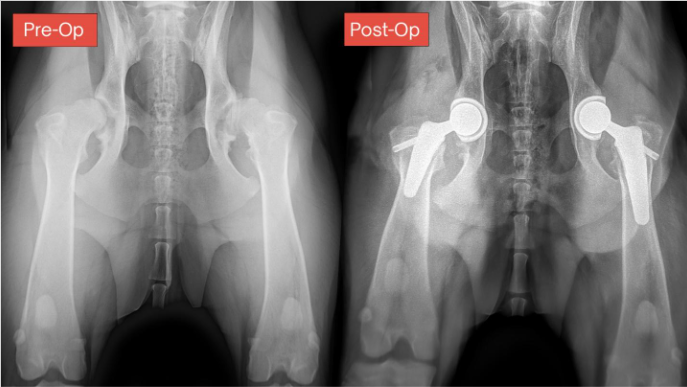

A total hip replacement (THR) procedure replaces both the head of the femur (‘ball’) and the acetabulum (‘socket’) of the hip joint (‘ball-and-socket’ joint) resulting in a complete arthroplasty. At AVES we use state of the art surgical implants, BioMedtrix total hip arthroplasty. These prosthetic implants are designed to function in the same manner as a healthy pain free joint, all while minimizing post-operative complications. THR is performed by surgeons who are board certified though the American College of Veterinary Surgeons (ACVS) and who have received specialized extensive training and certification in performing total hip arthroplasty, giving your pet the best chance for an excellent pain-free and functional outcome.

For over three decades, total hip replacement has been the gold standard treatment for pets with severe hip dysplasia and/or osteoarthritis, especially when conservative measures like medication or rehabilitation therapy are no longer working. A THR involves replacing the abnormal hip joint surfaces with a new prosthetic ‘ball and socket’ joint. These implants are made from specific metals, polyethylene plastic, and ceramics, each of which has been uniquely designed for cats and dogs of all sizes. The prosthesis is designed to fit precisely and mimics the anatomy of the original joint.

BioMedtrix proudly introduced the CFX® (Cement Fixation) Total Hip System in 1990, and the BFX® (Biologic Fixation – non-cemented) system in 2003. Since then, over 85,000 joint replacement procedures have been performed. The implants in each system are interchangeable and are prepared to a common surgical preparation with a set of specific instruments, providing greater versatility in the clinical options for total hip replacement. THR can be performed on dogs ranging from 4 through 170 pounds, and on cats.

When performed by a skilled THR surgeon, a THR procedure can have a 90-95% success rate for excellent hip function for the rest of your pet’s life. With advances in technology and techniques, today’s THR implants are designed to last for the lifetime of the pet.